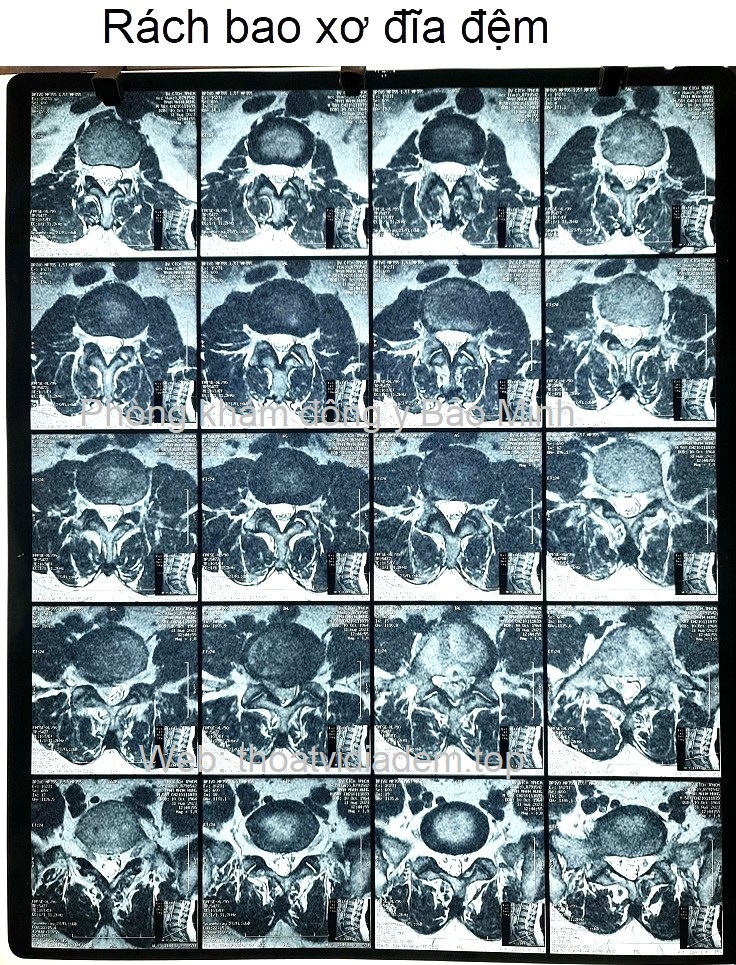

Rách bao xơ đĩa đệm Rách bao xơ đĩa đệm hay còn gọi là rách vòng xơ đĩa đệm. Khi bao xơ bị rách làm cho nhân nhầy đĩa đệm thoát ra ngoài gây nên bệnh thoát vị đĩa đệm. Điều trị rách bao xơ đĩa đệm phải dùng những vị thuốc có tác dụng chữa lành vết thương, vết rách. Khi thuốc ngấm vào cơ thể giúp hồi phục bao xơ đĩa đệm, giúp gân cơ dây chằng chắc khỏe dẻo dai, chữa hết bệnh vài năm sau cũng không bị đau nhức trở lại.❮ đọc tiếp ❯